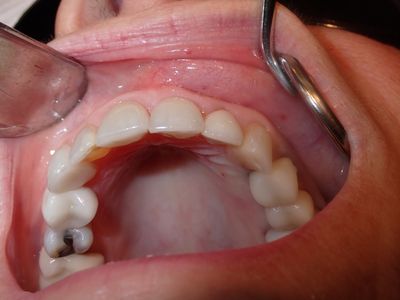

Atraumatic exo, loss of labial plate mid root about 2-3mm, CEJ and apical bone intact, region of thinner Labial-palatal bone, flapped site. osteotomy underprepared, implant placed with excellent stability. Buccal and socket grafted with 90/10 mix of mineralized cortical/xenograft followed by collagen membrane outside of socket on buccal, implant loaded with temporary crown out of centric and protrusive occlusion